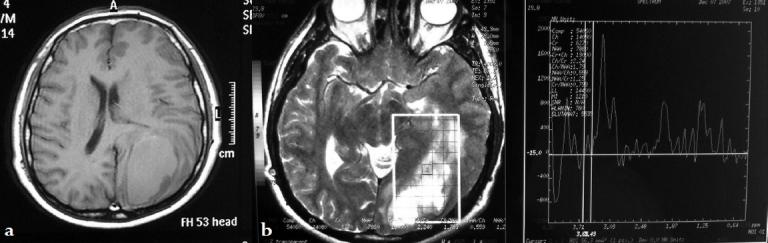

Unusual manifestations of primary Glioblastoma Multiforme: A report of three cases.

Surg Neurol Int. 2010 Dec 22;1:87. doi: 10.4103/2152-7806.74146.